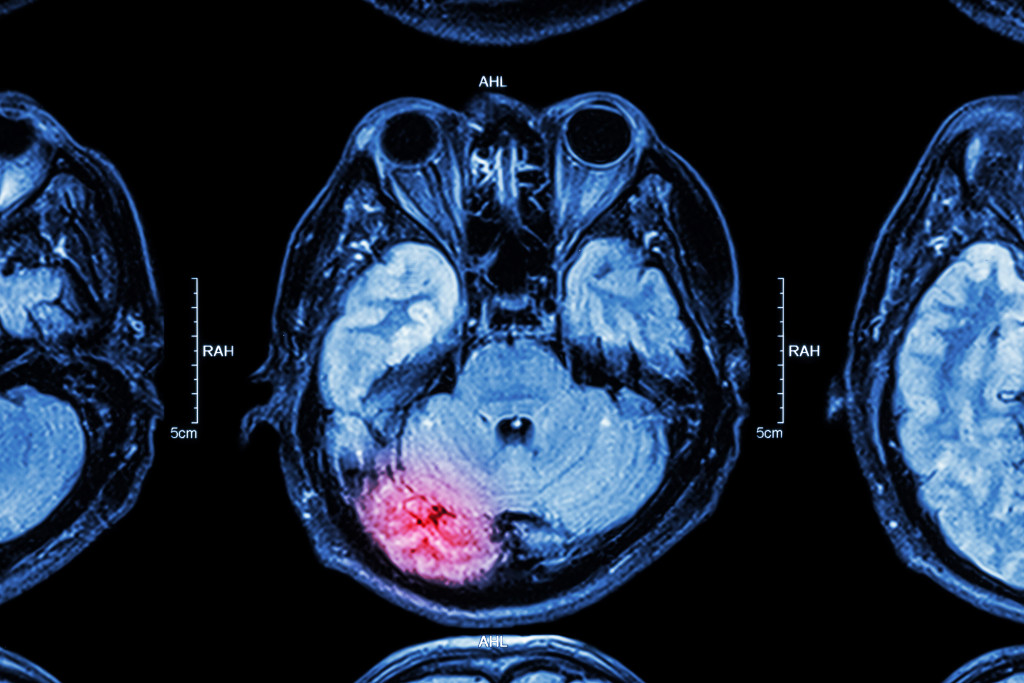

A traumatic brain injury (TBI) can be one of the most catastrophic injuries a victim can suffer in a personal injury accident.

A traumatic brain injury can be described in terms of the mechanism; that is, how the brain injury is sustained. A piercing injury occurs when the skull and brain cavity is actually penetrated by a foreign object (like a sharp tool or knife). An acceleration/deceleration injury occurs when the head is whipped violently back and forth (such as in a car accident) and the brain is thrown against the interior of the skull. A blunt force injury occurs when the head is struck by a blunt object (such as a board or a low ceiling).

A TBI can also be classified as mild, moderate, or severe based on the severity of the symptoms experienced. Some of the more common symptoms measured to assess TBI severity include post-traumatic amnesia (memory loss) and loss of consciousness. In general: